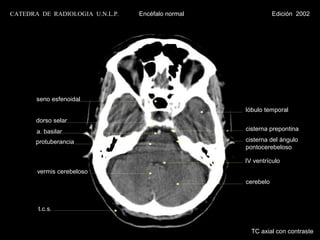

TC axial con contraste

CATEDRA DE RADIOLOGIA U.N.L.P.   Encéfalo normal              Edición 2002

globo ocular

lóbulo temporal

c.a.e.

bulbo

cerebelo

cisterna magna